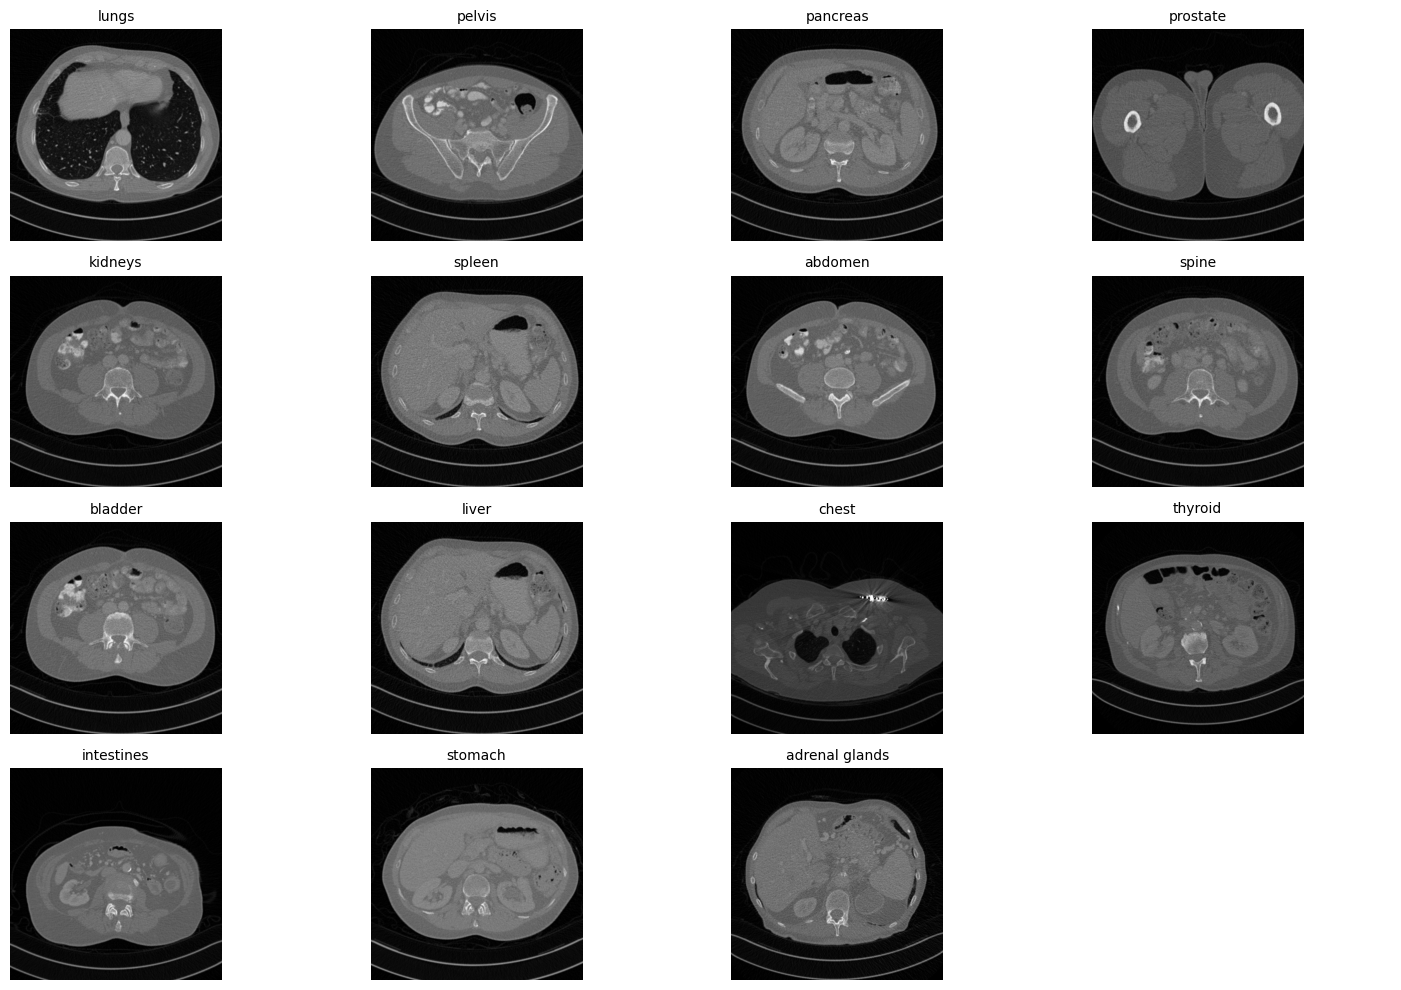

To simulate the training of anatomy-specific denoising models, we group Mayo-2016 dataset into three clusters based on captioning results from a medical vision-language embedding model, BiomedCLIP [24]. We first process each image through the model to extract embedding vectors that represent semantic similarities to twenty anatomical structures. The list of structures is shown in Figure 3 and their visual representations can be found in Appendix B.

Appendix B Anatomical Details

[Uncaptioned image]

Figure 8: Examples of 15 anatomical structures in the Mayo-2016 Dataset.